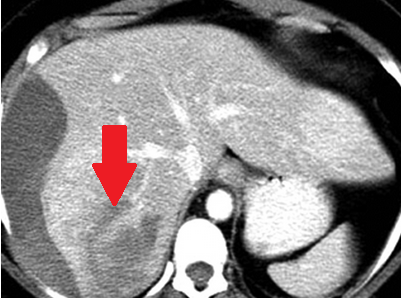

Αυτόματη ρήξη/αιμορραγία νεφρού — νεφροκυτταρικό καρκίνωμα (Ευγενική παραχώρηση Dr. V. Penopoulos)